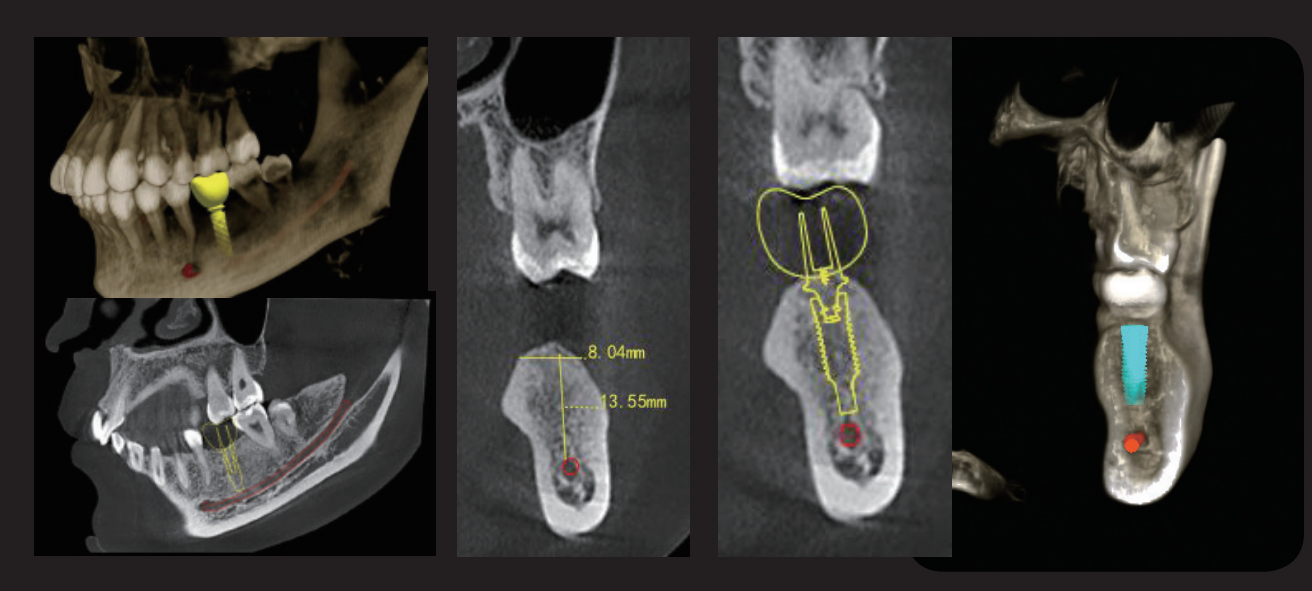

LargeV AI Implant integrates advanced AI technology to automatically measure bone height, bone width, and the distance to adjacent teeth. It intelligently recommends suitable implant models and enables automatic implant placement. This helps doctors complete precise implant planning in a short Hora, significantly enhancing the accuracy and safety of implant surgeries, while providing patients with a more reliable digital implant solution.

Implant Simulation

It can evaluate the bone quality and bone quantity of the implant area, automatically outline the neural tube. Clarifying the relationship between the implant position and the adjacent anatomical structure to accurately select the implant position, the optimal length and diameter of the implant. It can improve the success rate, and avoid possible nerve or blood vessel damage.

IA + Nervio

This function can locate the shape of the inferior alveolar nerve in 3D space, as well as the positional relationship between the relative alveolar bone wall, adjacent teeth, and implants, providing a reference for doctors, greatly improving work efficiency and reducing surgical risks.